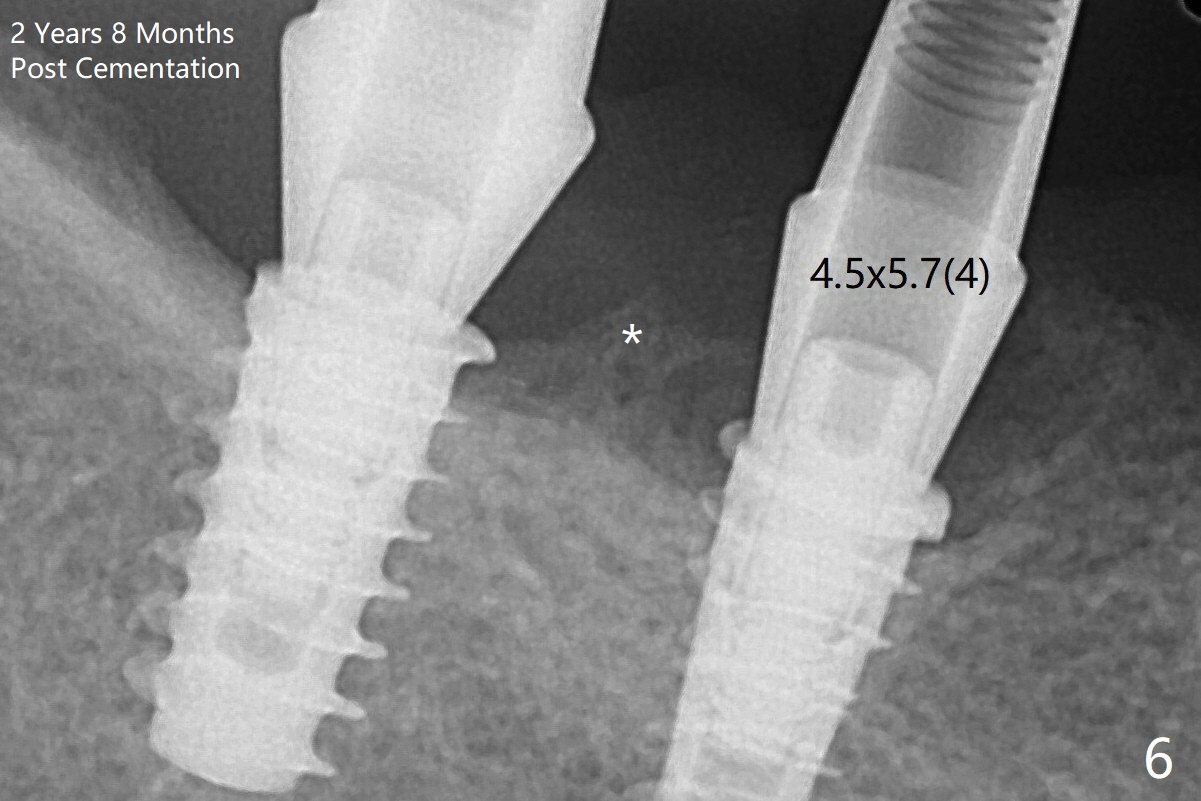

Note bone growth, especially at #30, 2.5 and 4 months postop (Fig.3,4). In fact the abutments are incompletely seated. The crown of #30 is loose with foul smell 2 years 8 months post cementation. It is painful to reinsert the crown/abutment after proximal reduction. A healing abutment is placed (Fig.5). When the incompletely seated abutment at #31 is removed, there is also smell. After separation from the crown, the abutment of #31 returns to the site with change in insertion position, while a smaller abutment has to be used at #30 (Fig.6) due to use of the small healing abutment earlier (Fig.5). A good piece of news is the presence of the bone between the implants (Fig.5,6 *), which contributes to interimplant papilla.